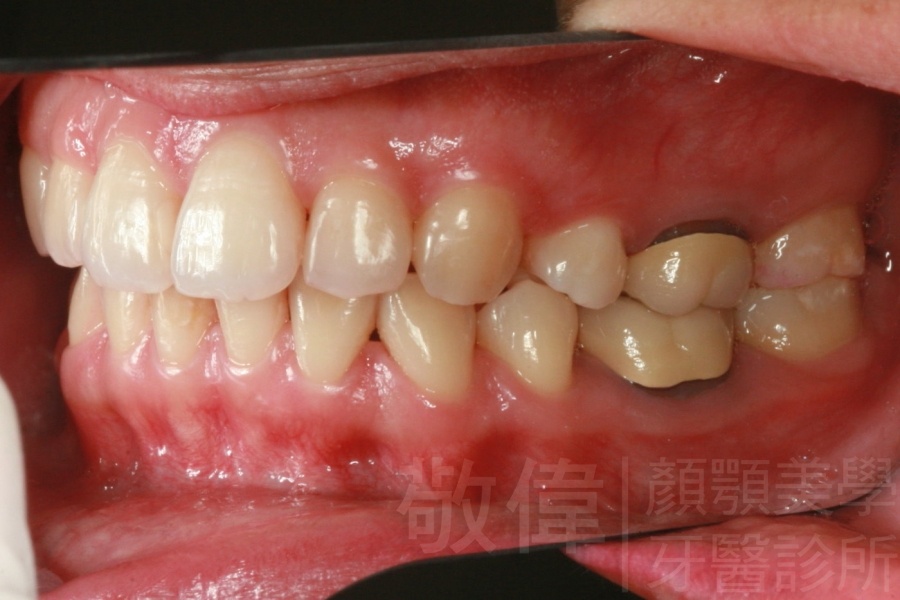

齒顏矯正/上顎暴牙且牙齒極度混亂

矯正前-右   矯正前-正   矯正前-左

<個案說明>

上顎暴牙且牙齒極度混亂,經由矯正之後,臉型大幅度改善,牙齒的排列更加的整齊健康。相較於之前眼神充滿精神,自信心展現無遺。